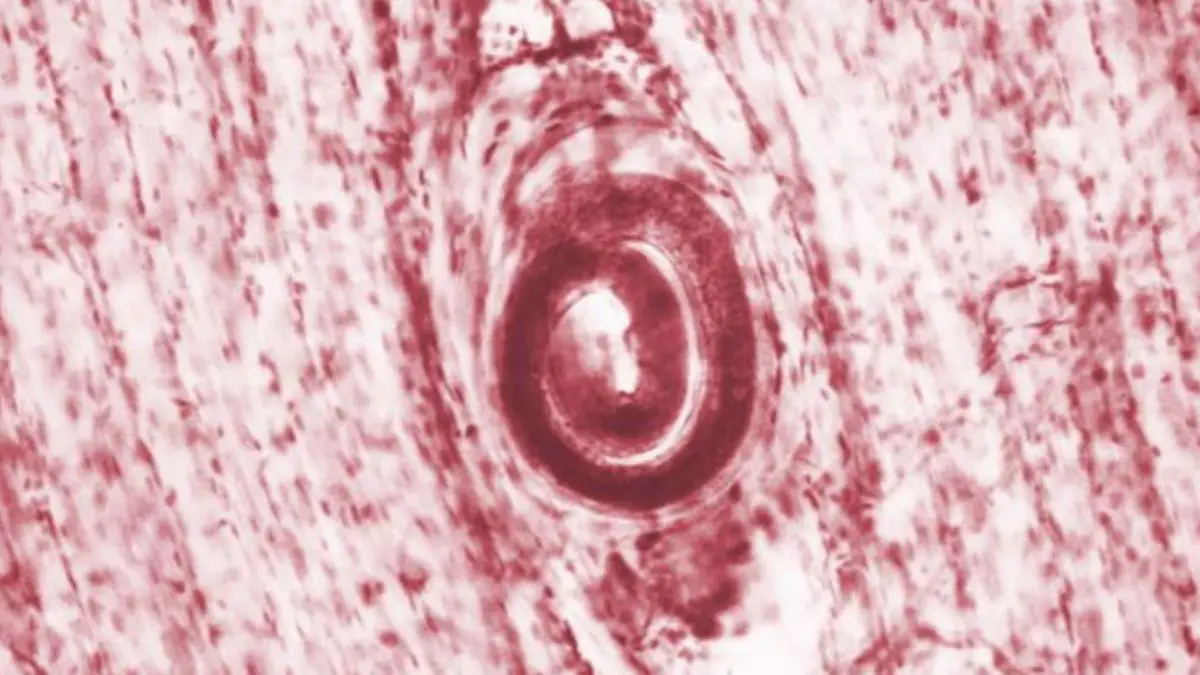

Трихинелла микроскоп

Трихинелла микроскоп 109 фотографий